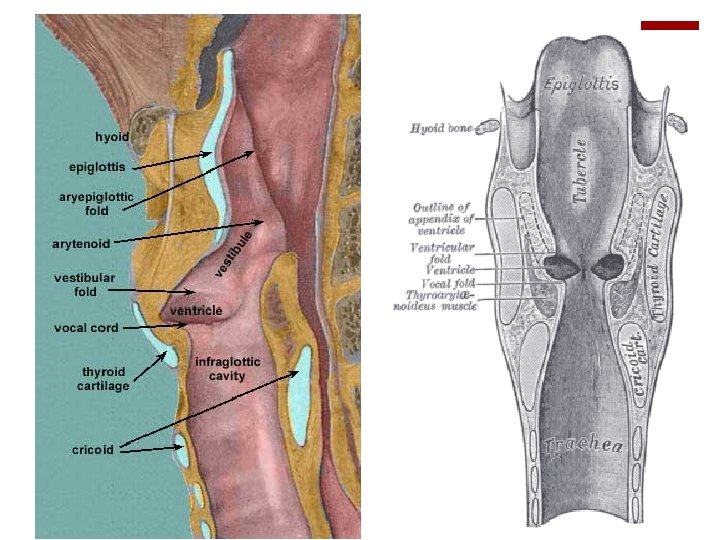

Laringocele ¡Herniación de la mucosa laríngea que se origina en el extremo apendicular del ventrículo. ¡Se haya en comunicación con el lumen laríngeo y su contenido es aire. ¡Moco ¡Sobreinfección laringopiocele ¡Más frecuentemente en el sexo masculino (7: 1) ¡ 5 ta-6 ta década de la vida ¡Ocurre general/ en pacientes que presentan períodos prolongados de aumento de la presión intralaríngea. ¡Incidencia es baja ¡ 1/2. 500. 000 habitantes ¡Naturaleza benigna, en principio, puesto que pueden albergar un

Etiología ¡ Etiología no es clara dilatación del sáculo laríngeo. ¡ El sáculo o apéndice laríngeo es un vestigio embrionario. ¡ Análogo a la vesícula aérea de los grandes primates? ? ? ¡ función es aumentar la resonancia? ? ? ¡ Lubricación de la mucosa de las cuerdas vocales? ¡ Histología: epitelio cilíndrico ciliado pseudoestratificado con 60 a 70 glándulas mucosas. ¡ Anatómicamente es un fondo de saco cuyo orificio comunica con el ventrículo laríngeo.